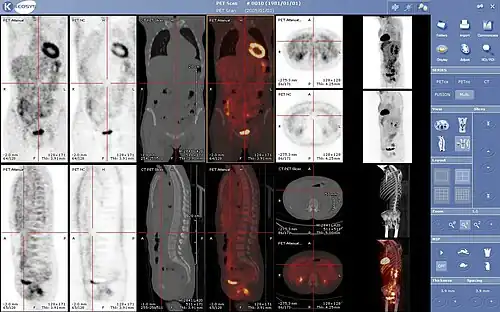

Nella seguente categoria sono incluse per lo più le apparecchiature utilizzate in medicina nucleare e radiologia che sfruttano tecniche di imaging a scopo diagnostico.

Tra gli esempi più rappresentativi ricordiamo la radiografia a raggi X, la tomografia computerizzata (TC), l'imaging a risonanza magnetica (MRI), la tomografia ad emissione di positroni (PET), la tomografia computerizzata ad emissione di singolo fotone (SPECT), l'ecografia ecc.

Inoltre l'informatica biomedica affronta il problema della trasmissione ed indicizzazione delle immagini ottenute da dispositivi digitali di acquisizione (TAC, MRI, ecc). Il problema riguarda sia la trasmissione di immagini per applicazioni di telemedicina sia l'immagazzinamento dei dati in appositi server digitali (PACS). Di fondamentale importanza in questo campo è l'uso del protocollo DICOM per la codifica delle immagini mediche digitali.

L'informatica biomedica affronta il problema dell'elaborazione delle immagini, come la visualizzazione tridimensionale. Di grande interesse è il campo della fusione di immagini, in cui immagini provenienti da diverse modalità di acquisizione vengono combinate per fornire al medico le informazioni in modo integrato.